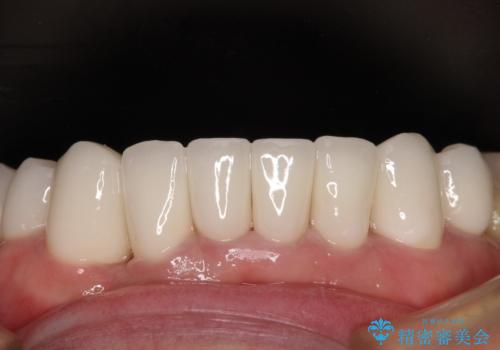

上下ともに前歯のセラミッククラウンによる補綴治療を希望されていましたが、下顎前歯は叢生が強いため、補綴治療前に部分矯正を行って歯列を整えた上で、補綴治療を行うこととしました。

ディープバイトにより臼歯部に負担のかかる咬合であったので、補綴治療後には、矯正治療の後戻り防止もかねて、睡眠時にマウスピースを装着するように指示しました。